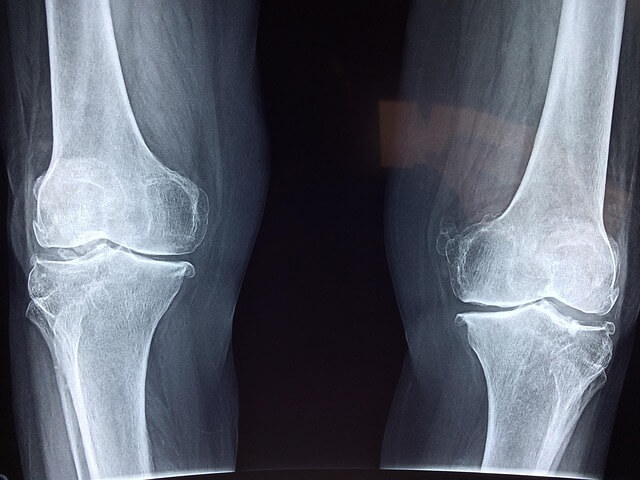

저 역시 서울에 있는 류마티스 내과를 다니다가 거리가 부담되어 집 근처 류마티스 내과로 병원을 옮긴 적이 있습니다. 그 과정에서 과거 진료기록을 미리 확인해 두었던 덕분에 중복 검사를 피하고 최소한의 비용으로 병원을 옮길 수 있었습니다.